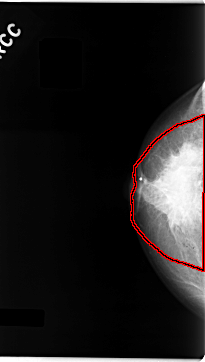

C_0061_1.RIGHT_MLO

RIGHT_MLO LINES 4680 PIXELS_PER_LINE 2536 BITS_PER_PIXEL 12 RESOLUTION 50 OVERLAY

FILE: C_0061_1.RIGHT_MLO.OVERLAY

TOTAL_ABNORMALITIES 2

ABNORMALITY 1

LESION_TYPE MASS SHAPE ROUND MARGINS CIRCUMSCRIBED

ASSESSMENT 5

SUBTLETY 5

PATHOLOGY MALIGNANT

TOTAL_OUTLINES 1

BOUNDARY

ABNORMALITY 2

LESION_TYPE MASS SHAPE IRREGULAR MARGINS SPICULATED